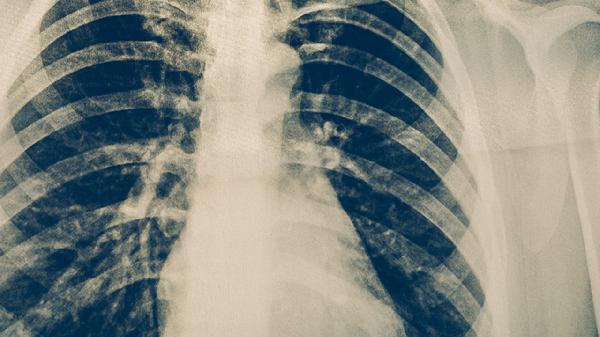

咯血表現(xiàn)為痰中帶血絲或少量鮮血,因腫瘤組織血供豐富且質(zhì)地脆弱,咳嗽時(shí)易導(dǎo)致血管破裂出血。中央型肺癌更易出現(xiàn)此癥狀,嚴(yán)重者可發(fā)生大咯血。需與肺結(jié)核、支氣管擴(kuò)張等疾病鑒別。診斷時(shí)可使用乙酰半胱氨酸泡騰片促進(jìn)排痰,酚磺乙胺注射液止血,必要時(shí)需行支氣管動(dòng)脈栓塞術(shù)。

胸痛常表現(xiàn)為胸部隱痛或鈍痛,在咳嗽或深呼吸時(shí)加重。當(dāng)腫瘤侵犯胸膜或胸壁時(shí)疼痛更為明顯,可能向肩背部放射。晚期肺癌侵犯肋間神經(jīng)可導(dǎo)致持續(xù)性劇痛。臨床常用布洛芬緩釋膠囊、塞來(lái)昔布膠囊緩解疼痛,嚴(yán)重者需使用鹽酸嗎啡緩釋片。合并胸腔積液時(shí)可進(jìn)行胸腔穿刺引流。

肺癌患者應(yīng)嚴(yán)格戒煙并避免二手煙,保持居住環(huán)境空氣流通。飲食宜選擇高蛋白食物如魚肉、蛋類,搭配西藍(lán)花、胡蘿卜等富含抗氧化物質(zhì)的蔬菜。可進(jìn)行散步、太極拳等低強(qiáng)度運(yùn)動(dòng),但避免劇烈活動(dòng)加重呼吸困難。定期復(fù)查胸部CT監(jiān)測(cè)病情變化,若出現(xiàn)聲音嘶啞、面部水腫等新癥狀需立即就診。心理疏導(dǎo)有助于緩解焦慮情緒,家屬應(yīng)給予充分情感支持。